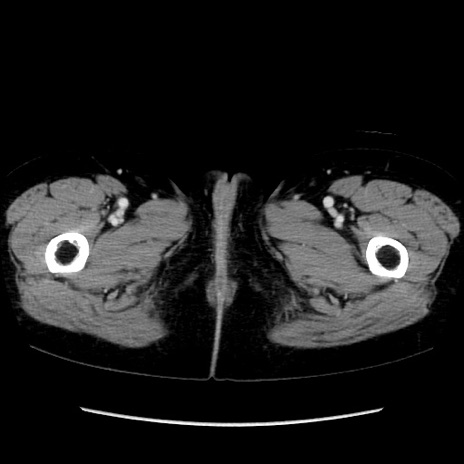

症例32(横断像)

【症例】40歳代 女性

【主訴】上腹部痛、嘔気・嘔吐

【現病歴】約9時間前頃から急に上腹部痛、嘔気、嘔吐が出現。改善しないため救急要請。

【既往歴】子宮頚癌(広汎子宮全摘術、放射線療法)、腸閉塞

【身体所見】腹部:平坦、軟、腸雑音亢進、上腹部を中心に腹部全体に圧痛あり。

【データ】WBC 8400、CRP 0.03